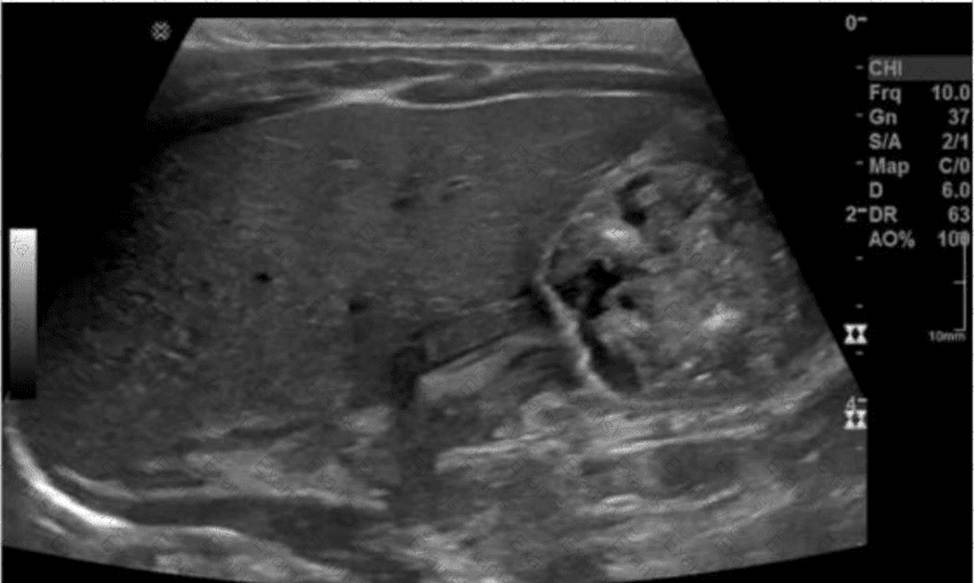

Which condition is demonstrated in this image of the groin?

The ultrasound image demonstrates bowel loops with peristalsis visualized within the inguinal canal, which is diagnostic of an inguinal hernia―more specifically, an indirect inguinal hernia. Indirect hernias pass through the deep inguinal ring and may extend into the scrotum, appearing sonographically as bowel-containing masses adjacent to or within the scrotal sac. Peristaltic motion confirms the presence of viable bowel content.

This finding is typical in indirect inguinal hernias, which are more common in males and often congenital due to a patent processus vaginalis. The herniated bowel can be traced through the inguinal canal, as seen in this image.

Comparison of answer choices:

A. Hematocele presents as a complex fluid collection surrounding the testis, often due to trauma―no complex fluid or trauma is apparent here.

B. Testicular rupture shows discontinuity of the tunica albuginea and irregular testicular contour―none of which is seen.

C. Orchiectomy would show an absent testis―this is not the case here.

D. Indirect hernia is correct. The presence of bowel with peristalsis in the inguinal canal is diagnostic.